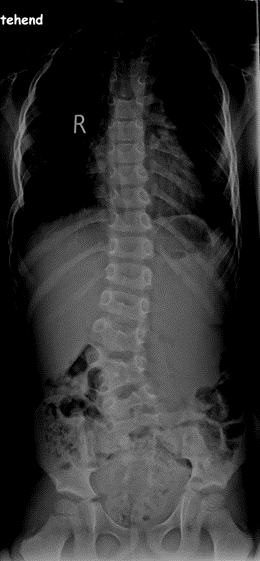

Linkskonvexe langbogige lumbale Krümmung mit Beckenschiefstand und Rumpfüberhang nach rechts bei 11 jährigem Rollstuhlfahrer:

Mit Hilfe einer Wirbelsäulenganzaufnahme, einem Röntgenbild der kompletten Wirbelsäule, können der Krümmungswinkel sowie die Verdrehung der Wirbelkörper gemessen werden. Es sollte immer die gesamte Wirbelsäule auf einer Aufnahme abgebildet und nicht mehrere kleine Bilder angefertigt werden, da man die Krümmung sonst nicht exakt vermessen und die Statik beurteilen kann.

Für diese Wirbelsäulenganzaufnahmen braucht man spezielle, sehr teure Röntgenröhren, die natürlich nicht jeder Arzt hat. Deswegen kann es sein, dass du in ein spezialisiertes Wirbelsäulenzentrum überwiesen wirst. Die Winkel werden in „Gradzahlen nach Cobb“ angegeben, da Dr. Cobb diese Messmethode entwickelt hat. Vor einer Operation werden noch sogenannte Bending-Aufnahmen angefertigt. Du musst dich einmal so weit es geht nach links und dann nach rechts biegen. Danach kann man ausmessen, welche Krümmung schon steif (rigide) ist und welche noch so flexibel ist, dass sie sich noch selbständig ausgleichen kann. Das ist vor allem für die OP-Planung wichtig.